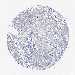

CERVICAL CANCER - Protein expressioni

A mouse-over function shows sample information and annotation data. Click on an image to view it in a full screen mode. Samples can be filtered based on level of antibody staining by selecting one or several of the following categories: high, medium, low and not detected. The assay and annotation is described here.

Note that samples used for immunohistochemistry by the Human Protein Atlas do not correspond to samples in the TCGA dataset.

Antibody stainingi

Antibody staining in the annotated cell types in the current human tissue is reported as not detected, low, medium, or high, based on conventional immunohistochemistry profiling in selected tissues. This score is based on the combination of the staining intensity and fraction of stained cells.

Each image is clickable and will lead to virtual microscopy that enables deeper exploration of all samples and also displays staining intensity scores, fraction scores and subcellular localization as well as patient and tissue information for each sample.

Antibody CAB039239

Adenocarcinoma, NOS